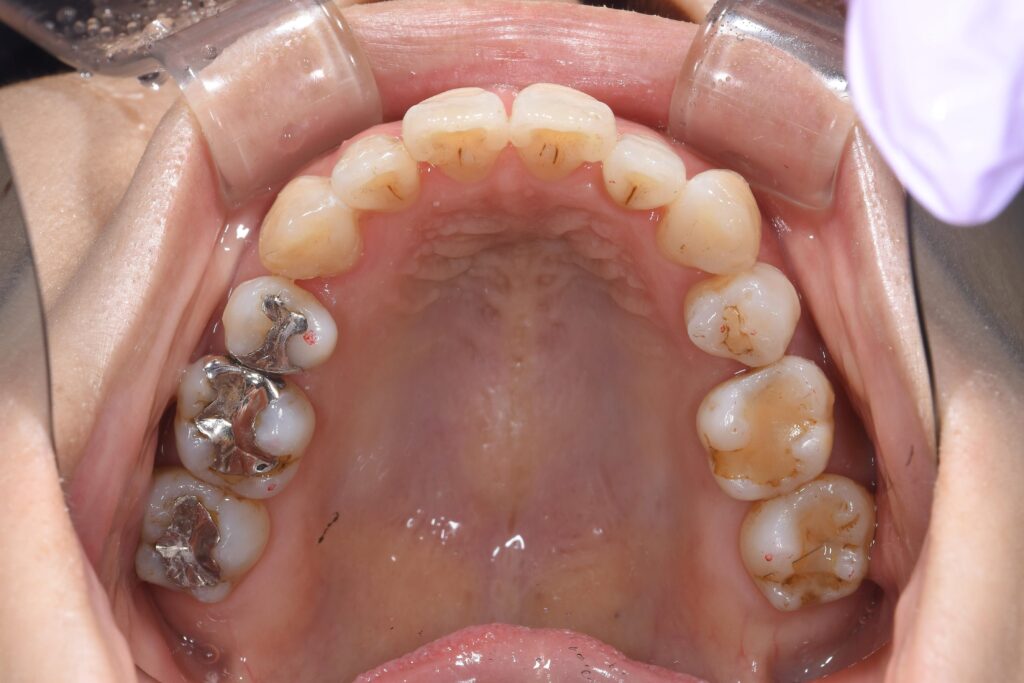

まずは矯正開始前の状態です。

写真が暗くて申し訳ございません。

【矯正開始前】

この患者様の問題点を以下に列挙します。

【問題点】

①歯のががたつきが強く、清掃困難な状態である。

②かみ合わせに問題があり、左上5番目の歯が歯周病で保存困難となったため、抜歯が必要となった。

③歯を並べるスペースが窮屈であり、スペース獲得のため便宜的な抜歯治療が必要である。

大まかに上記3点となります。